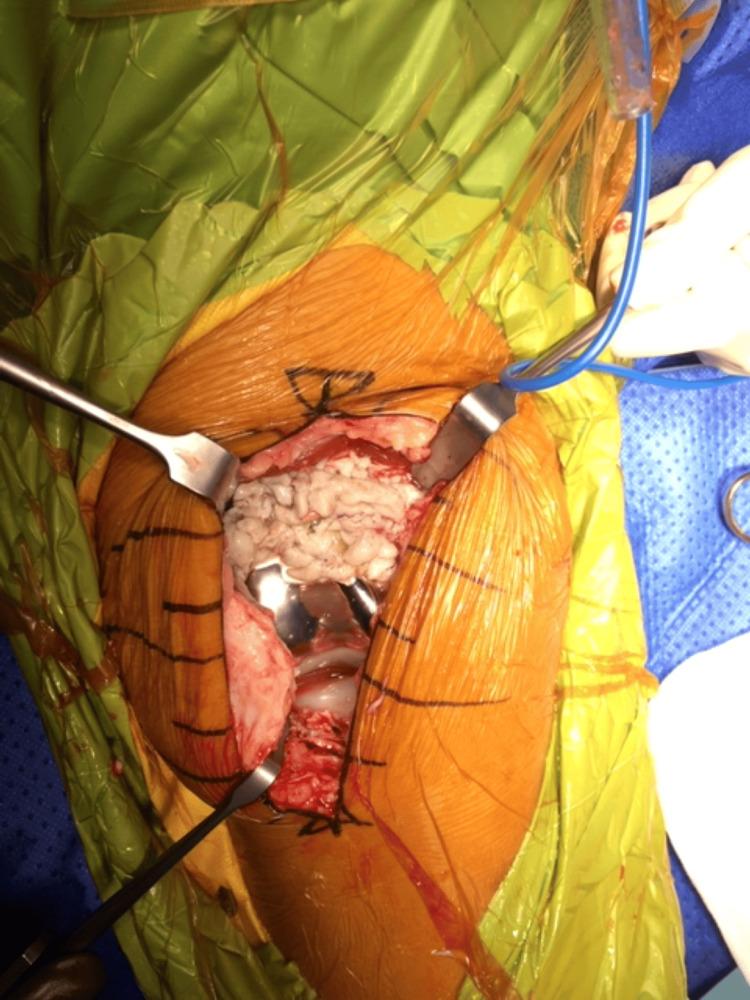

Particulate wear is a well-established cause of aseptic loosening and failure in joint arthroplasty. We aim to describe a case of cement-induced synovitis with the deposition of cement debris causing a distinct green-hued synovitis in a case of primary total knee arthroplasty (TKA). A 61-year-old lady presented to our clinic with right knee pain and swelling after undergoing bilateral total knee replacement four years ago at another institution. She was initially worked up by her primary surgeon and was symptomatically treated with non-steroidal anti-inflammatory medication (NSAID). However, her symptoms persisted and impaired her daily function. She presented with right knee effusion and decreased range of motion of the knee, as well as joint line tenderness. Further radiological investigations showed right knee tibial component implant loosening, with bone cement fragments in the anterior tibia. As such, the patient was counselled and underwent a revision surgery. Intraoperatively, there was extensive synovitis with prominent green pigment deposits. Excessive cement was noted in the femoral notch, causing wear of the liner pole. The tibia tray was also found to be loose, with no cement adherent to the tibia tray, and all the cement mantle seated on the tibia bone. Postoperatively, the patient made an uneventful recovery. She was able to range her knee from 10-130 degrees with no pain within 2 months. Direct wear from residual cement and micromotion at the tibia tray due to poor cementing technique during the primary surgery were important factors leading to severe cement wear and failure. This clinical case is a reminder of the importance of good cementing technique to ensure a good outcome in TKA.

颗粒磨损是关节置换术中无菌性松动和失败的一个公认原因。我们旨在描述一例水泥诱导的滑膜炎病例,在初次全膝关节置换术(TKA)中,水泥碎屑的沉积导致了一种独特的绿色滑膜炎。一名61岁女性四年前在另一家机构接受双侧全膝关节置换术后,因右膝疼痛和肿胀前来我院就诊。她最初由主刀医生进行检查,并接受了非甾体类抗炎药(NSAID)的对症治疗。然而,她的症状持续存在,影响了她的日常功能。她出现右膝关节积液、膝关节活动范围减小以及关节线压痛。进一步的影像学检查显示右膝胫骨部件植入物松动,胫骨前方有骨水泥碎片。因此,对患者进行了咨询并接受了翻修手术。术中发现广泛的滑膜炎,有明显的绿色色素沉着。在股骨切迹处发现过多的骨水泥,导致衬垫杆磨损。还发现胫骨托盘松动,胫骨托盘上没有骨水泥附着,所有骨水泥套都位于胫骨骨上。术后,患者恢复顺利。她能够在2个月内将膝关节活动范围从10度扩大到130度,且无疼痛。初次手术时由于骨水泥技术不佳导致的残留骨水泥直接磨损和胫骨托盘处的微动是导致严重骨水泥磨损和失败的重要因素。这个临床病例提醒我们良好的骨水泥技术对于确保TKA取得良好结果的重要性。